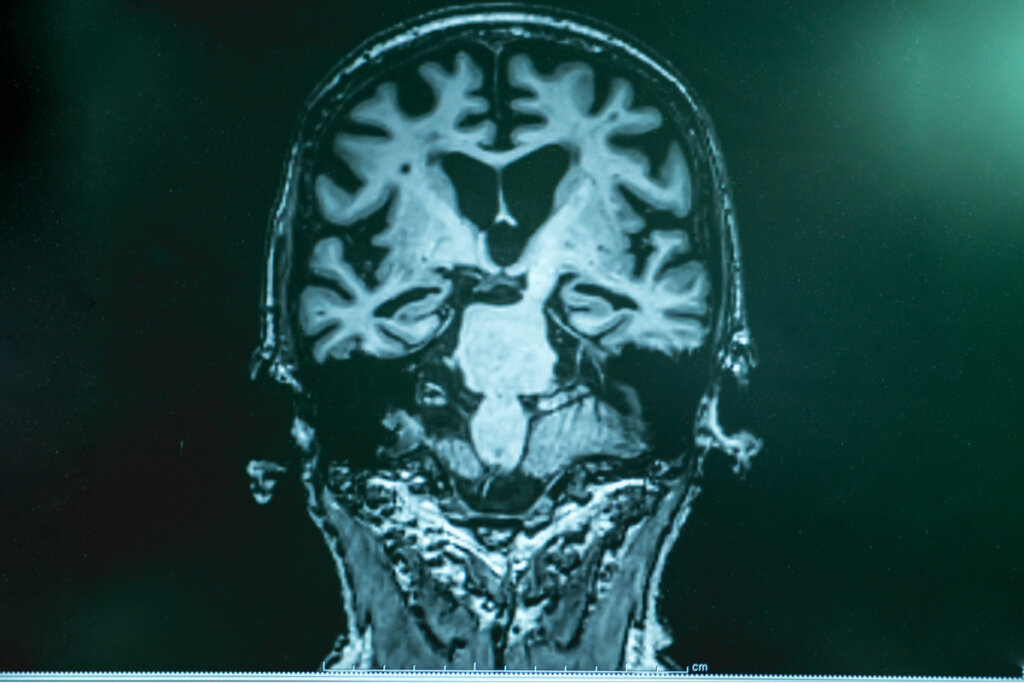

El origen y la causa de la enfermedad de Alzheimer son aún un misterio. De hecho, el diagnóstico solo puede ser confirmado postmortem. En vida, el diagnóstico se queda en “enfermedad de Alzheimer probable o posible”. Por ello, la investigación para lograr determinar la causa de esta enfermedad está muy viva.